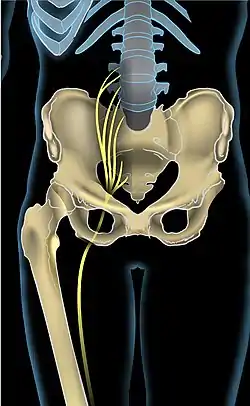

The sciatic nerve, also called the ischiadic nerve, is a large nerve in humans and other vertebrate animals which is the largest branch of the sacral plexus and runs alongside the hip joint and down the lower limb. It is the longest and widest single nerve in the human body, going from the top of the leg to the foot on the posterior aspect. The sciatic nerve has no cutaneous branches for the thigh. This nerve provides the connection to the nervous system for the skin of the lateral leg and the whole foot, the muscles of the back of the thigh, and those of the leg and foot. It is derived from spinal nerves L4 to S3. It contains fibers from both the anterior and posterior divisions of the lumbosacral plexus.

Structure

In humans, the sciatic nerve is formed from the L4 to S3 segments of the sacral plexus, a collection of nerve fibres that emerge from the sacral part of the spinal cord. The lumbosacral trunk from the L4 and L5 roots descends between the sacral promontory and ala and the S1 to S3 roots emerge from the ventral sacral foramina. These nerve roots unite to form a single nerve in front of the piriformis muscle. The nerve passes beneath piriformis and through the greater sciatic foramen, exiting the pelvis.[1]: 422–4 From here, it travels down the posterior thigh to the popliteal fossa. The nerve travels in the posterior compartment of the thigh behind (superficial to) the adductor magnus muscle, and is itself in front of (deep to) the long head of the biceps femoris muscle. At the popliteal fossa, the nerve divides into its two branches:[1]: 532

Sciatic nerve.